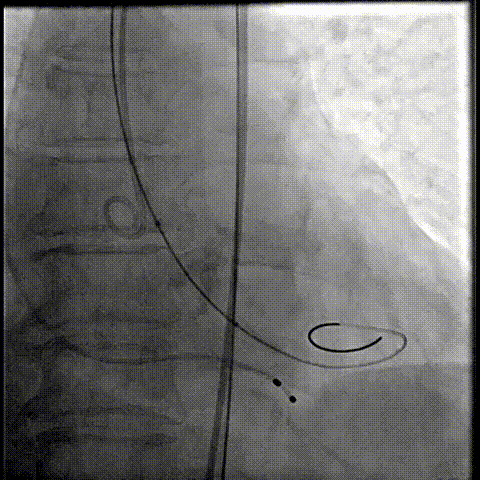

器械过弓柔顺

初始定位